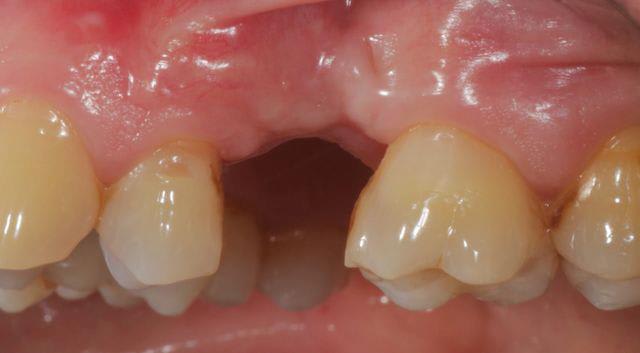

tiens pour faire avancer le débat un cas de ROG verticale et horizontale, avec membrane PTFE armé titane.

486849 10151469282438909 1569932967 n wfvtaw - Eugenol

67354 10151469282783909 1467702450 n qvjnob - Eugenol

563553 10151469282653909 1593165568 n dihjew - Eugenol

1853 10151469282613909 1015929230 n hhsfft - Eugenol

555374 10151469088933909 1265673870 n ui2jmo - Eugenol

72650 10151469088903909 1954739928 n ygymol - Eugenol

450 10151469088763909 748076808 n aldyeu - Eugenol

421967 10151469088718909 212073595 n t3r6tw - Eugenol